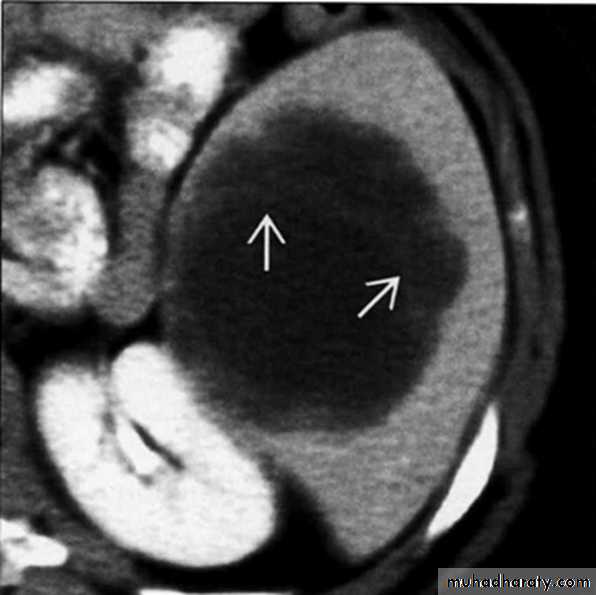

Pyogenic splenic abscess on axial CECT.Note thin septations within abscess (arrows)